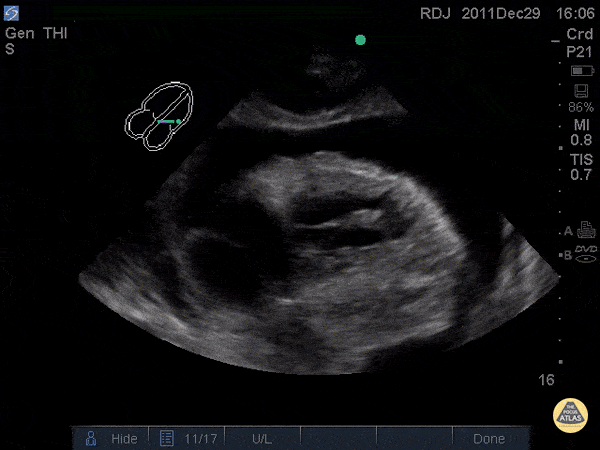

D Sign + McConnell's Sign

Evidence: https://www.ncbi.nlm.nih.gov/pubmed/26973178

Example: http://www.thepocusatlas.com/right-ventricle

Tutorial: https://westernsono.ca/screencasts/echo/mcconnells-sign-acute-pulmonary-embolism/